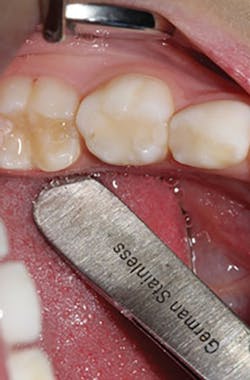

The steps for preparation and cementation were as follows. First, local anesthesia was delivered. Second, isolation was achieved with an isolation system (Isodry). Third, preparation steps were undertaken: Occlusal preparation was completed using a high-speed handpiece with copious amounts of water and a coarse, long-tapered diamond bur (NuSmile) to achieve an occlusal reduction of 1.5–2 mm. Circumferential reduction of approximately 15–20% was carried out using the same bur. In order to visualize the completeness and evenness of the preparation, a full circumferential reduction supragingivally was completed at this stage. A subgingival preparation was again completed using a high-speed handpiece with copious water and a finer, more tapered diamond bur (NuSmile). As required, a full subgingival reduction to approximately 1.5 mm depth was achieved, ensuring no ledges and a smooth featheredge margin (figure 2). It was essential that the crown fit passively and be able to be seated completely unencumbered. In order to ensure fit and occlusion and to prevent contamination of the zirconia crown to be cemented, a Try-In crown (NuSmile) was used (figure 3). Refinements to the preparation to facilitate fit and occlusion were done at this point.

Figure 2: Full subgingival reduction to approximately 1.5 mm depth